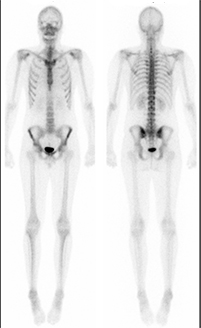

Unauffälliges Skelettszintigramm eines jungen Mannes.

Die Untersuchung wird meist in Mehrphasentechnik durchgeführt, was bedeutet, dass die ersten Aufnahmen bereits direkt nach Injektion des Radiopharmakons angefertigt werden, um die Durchblutung einzelner Skelettabschnitte oder auch des Gesamtskeletts zu beurteilen. Danach können Sie die Praxis für einige Zeit verlassen. Die Aufnahmen des Knochenstoffwechsels erfolgen erst 2-3 Stunden nach der Injektion, so dass die Gesamtuntersuchungszeit durchaus 4 Stunden betragen kann, in Einzelfällen auch länger, je nach Fragestellung.

Multiple knöcherne Läsionen nach einem Fahrradsturz: Linkes Schultergelenk, Rippenserienfraktur, linkes Wadenbein. An den Frühaufnahmen (linkes Bild) stellen sich die frischen Herde mit verstärkter Durchblutung dar. Die Spätaufnahmen (rechtes Bild) dokumentieren den reparativ verstärkten Knochenstoffwechsel.